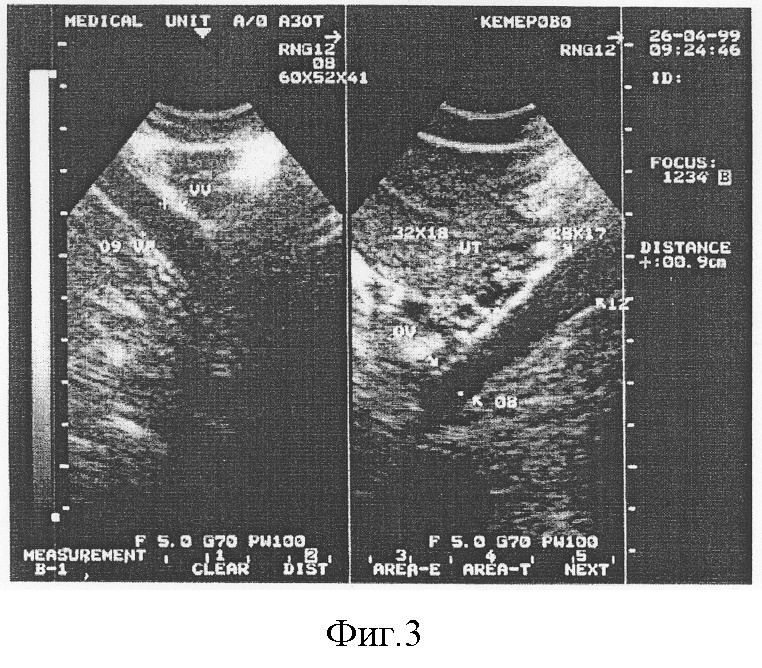

Для подтверждения диагноза проведено исследование согласно предлагаемому способу.

Получены следующие результаты: диаметр маточных вен составил 1,3 см справа и 1,1 см слева; диаметр внутренних подвздошных вен составил 2,4 и 2,1 см соответственно, диаметр яичниковых вен 0,6 и 0,7 см соответственно; диаметр аркуатных вен 0,6 см (фигура 2).

Проведенное исследование позволило обозначить полученные данные как варикозное расширение маточных, яичниковых, внутренних подвздошных и аркуатных вен, что позволило установить правильный диагноз у данного пациента.